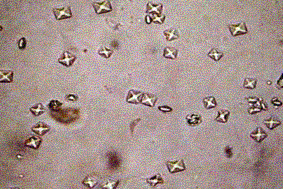

二水和盐:无色外壳或八面体装;一水合盐:针形或哑铃状

无色六边形板状